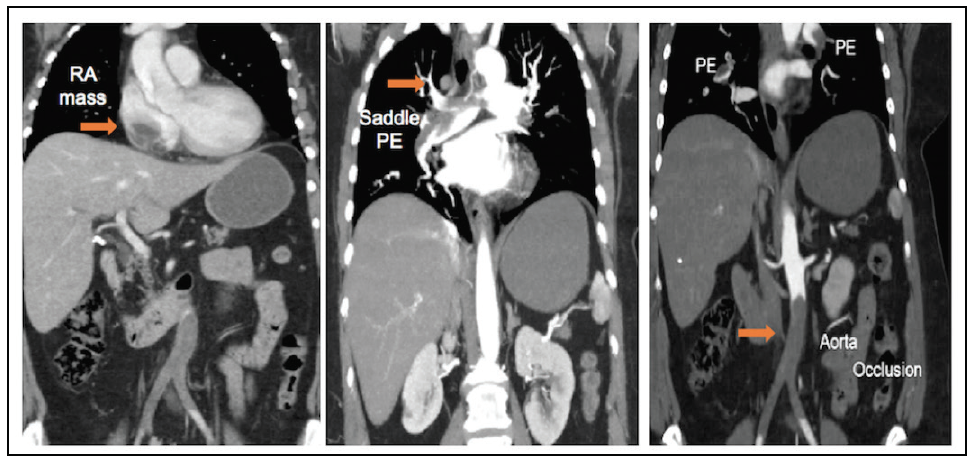

A 59-year-old woman presented with worsening dyspnea (1-week duration) and acute left lower extremity pain. Her medical history included diabetes mellitus, B-cell lymphoma (for which she was on current chemotherapy), and breast cancer (in remission after surgery and chest radiation). On presentation, the patient was tachypneic, mildly hypoxemic (oxygen saturation, 90% on 40% FiO2), and normotensive. Her left foot was cold, and the left femoral arterial pulse was absent. CT showed a saddle pulmonary embolism (PE), right atrial mass, and thrombotic occlusion of the distal aorta (Figure 1). She underwent emergent bilateral aortoiliac thrombectomy with a Fogarty catheter (Edwards Lifesciences), which resolved the leg ischemia. She was started on intravenous unfractionated heparin.

Given the active paradoxical embolization, the decision was made to perform PFO closure initially. This was successfully achieved with a 30-mm Cardioform device guided by intracardiac echocardiography without complications. The patient underwent a staged extraction of the right atrial mass with an AngioVac cannula 72 hours later. Pathologic examination of the extracted mass revealed predominantly thrombus without evidence of tumor (Figure 2). I agree with the panelists that a more aggressive approach to the PE could have been taken. However, concerns were raised about the use of tissue plasminogen activator (albeit locally) given the fresh femoral cutdown sites that were used to perform the aortoiliac thrombectomy.